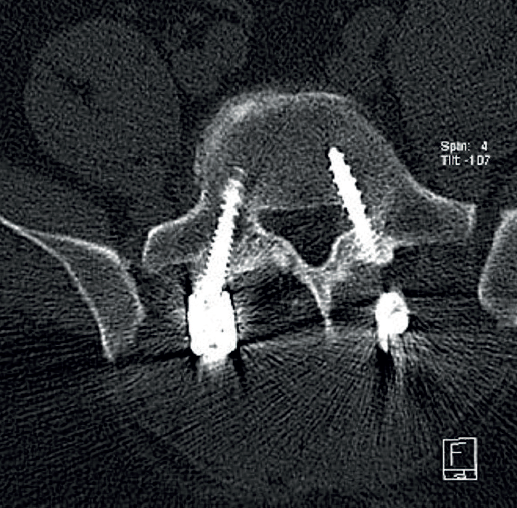

Se trata de un varón de 57 años, empleado en recogida de basura. Diez días antes de la consulta sufre una caída accidental con dolor intenso en el miembro inferior izquierdo, hipoestesia en calcetín y debilidad para la flexión y extensión del tobillo. En la exploración física presentaba Lasègue izquierdo negativo, derecho positivo a 50° y femoral stretch test derecho positivo. Se constató fuerza 1/5 en el tobillo izquierdo. La resonancia magnética (Figura 1) mostró discopatía L4-L5 con hernia discal posteromedial derecha. La electromiografía (EMG) evidenció afectación radiculoplexular izquierda moderada L3-L4 y grave L5-S1 posganglionar.

Figura 1. Resonancia magnética lumbar inicial. A: corte sagital en secuencia T2: discopatía de grado IV en L4-L5 con hernia discal extruida; B: corte axial en secuencia T1 a nivel de L4-L5, con estenosis del receso lateral derecho secundaria a extrusión discal; C: corte axial en secuencia T2, con protrusión discal difusa con estenosis foraminal bilateral y canal medular estrecho (grado C según Schizas-Theumann).